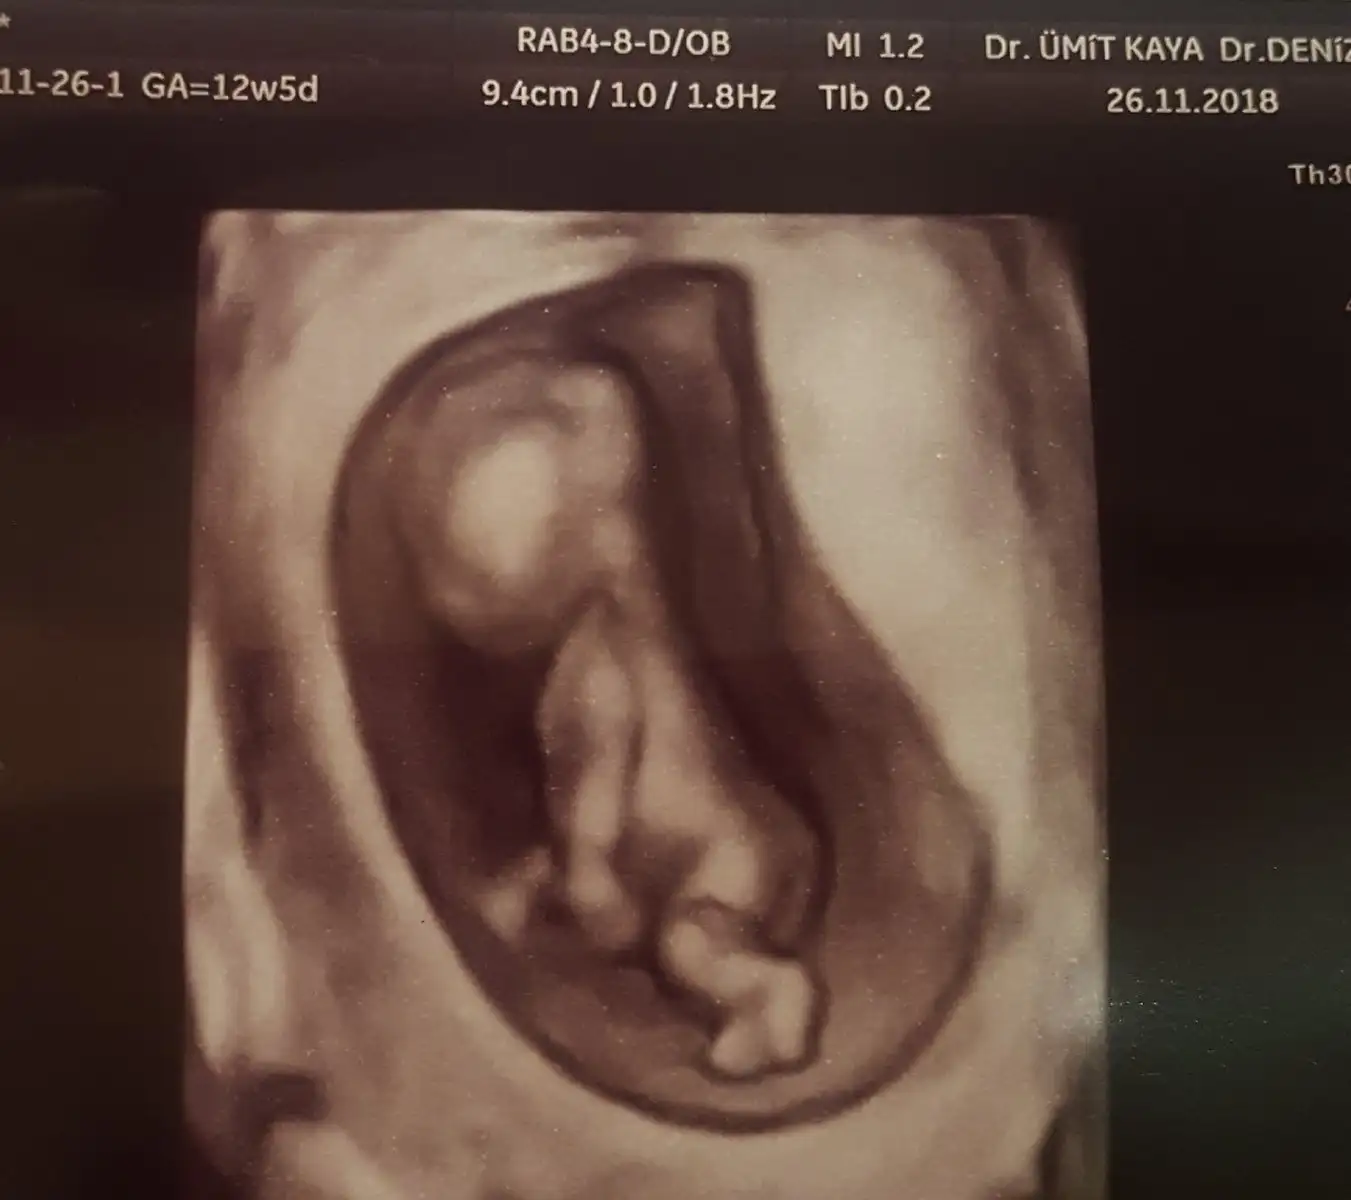

görülüyormuşum sevindim evet küçük biraz ben kafasını bile anlayamadım